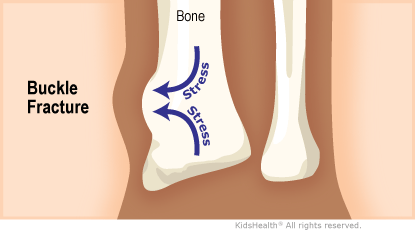

Buckle Fracture Symptoms Causes Treatment 2025, Buckle fracture of the wrist CUH 2025, Buckle Fracture Raleigh Hand Surgery Joseph J. Schreiber MD 2025, Fracture How to treat a buckle fracture of the distal radius 2025, Torus fracture Wikipedia 2025, Buckle fracture 2025, Kidshealth Buckle Fractures Akron Children s 2025, Buckle fractures of the distal radius in children CMAJ 2025, How to Care for Your Child with Buckle Fracture Sidra Medicine 2025, Kids Health Information Fracture care buckle injury 2025, The Pediatric Wrist Buckle Fracture is Common Louisville Bones 2025, Buckle fracture 2025, Forearm Fractures Children s Mercy Kansas City 2025, Buckle Fracture Raleigh Hand Surgery Joseph J. Schreiber MD 2025, Buckle Fractures Rady Children s Hospital 2025, Greenstick Buckle Fracture Activate Physiotherapy 2025, What are Buckle Fractures WristSupports 2025, Buckle Greenstick Fracture of the Distal Radius Sports 2025, Choosing Wisely Distal Radius Buckle Fractures CanadiEM 2025, Buckle Greenstick Fracture of the Distal Radius Sports 2025, Clinical Practice Guidelines Distal radius and or ulna 2025, Buckle fracture Radiology at St. Vincent s University Hospital 2025, Radiology Case 5 SpringerLink 2025, Buckle fracture of the wrist Resource Library Sheffield 2025, Forearm Fractures Children s Mercy Kansas City 2025, Buckle fracture Radiology Case Radiopaedia 2025, Fracture How to treat a buckle fracture of the distal radius 2025, Buckle fracture in a girl age 2 years 3 months who presented to 2025, Greenstick Fracture or Paediatric Fracture Treatment 2025, Buckle fracture Radiology Case Radiopaedia 2025, Buckle Fracture by Dr. David Nelson MD 2025, Pondering Paeds Buckle In 2025, State of the Art Pediatrics Buckle Fractures in Children 2025, OrthoKids Forearm Fractures 2025, Buckle Greenstick Fracture of the Distal Radius Sports 2025.

Buckle Fracture Symptoms Causes Treatment 2025, Buckle fracture of the wrist CUH 2025, Buckle Fracture Raleigh Hand Surgery Joseph J. Schreiber MD 2025, Fracture How to treat a buckle fracture of the distal radius 2025, Torus fracture Wikipedia 2025, Buckle fracture 2025, Kidshealth Buckle Fractures Akron Children s 2025, Buckle fractures of the distal radius in children CMAJ 2025, How to Care for Your Child with Buckle Fracture Sidra Medicine 2025, Kids Health Information Fracture care buckle injury 2025, The Pediatric Wrist Buckle Fracture is Common Louisville Bones 2025, Buckle fracture 2025, Forearm Fractures Children s Mercy Kansas City 2025, Buckle Fracture Raleigh Hand Surgery Joseph J. Schreiber MD 2025, Buckle Fractures Rady Children s Hospital 2025, Greenstick Buckle Fracture Activate Physiotherapy 2025, What are Buckle Fractures WristSupports 2025, Buckle Greenstick Fracture of the Distal Radius Sports 2025, Choosing Wisely Distal Radius Buckle Fractures CanadiEM 2025, Buckle Greenstick Fracture of the Distal Radius Sports 2025, Clinical Practice Guidelines Distal radius and or ulna 2025, Buckle fracture Radiology at St. Vincent s University Hospital 2025, Radiology Case 5 SpringerLink 2025, Buckle fracture of the wrist Resource Library Sheffield 2025, Forearm Fractures Children s Mercy Kansas City 2025, Buckle fracture Radiology Case Radiopaedia 2025, Fracture How to treat a buckle fracture of the distal radius 2025, Buckle fracture in a girl age 2 years 3 months who presented to 2025, Greenstick Fracture or Paediatric Fracture Treatment 2025, Buckle fracture Radiology Case Radiopaedia 2025, Buckle Fracture by Dr. David Nelson MD 2025, Pondering Paeds Buckle In 2025, State of the Art Pediatrics Buckle Fractures in Children 2025, OrthoKids Forearm Fractures 2025, Buckle Greenstick Fracture of the Distal Radius Sports 2025.